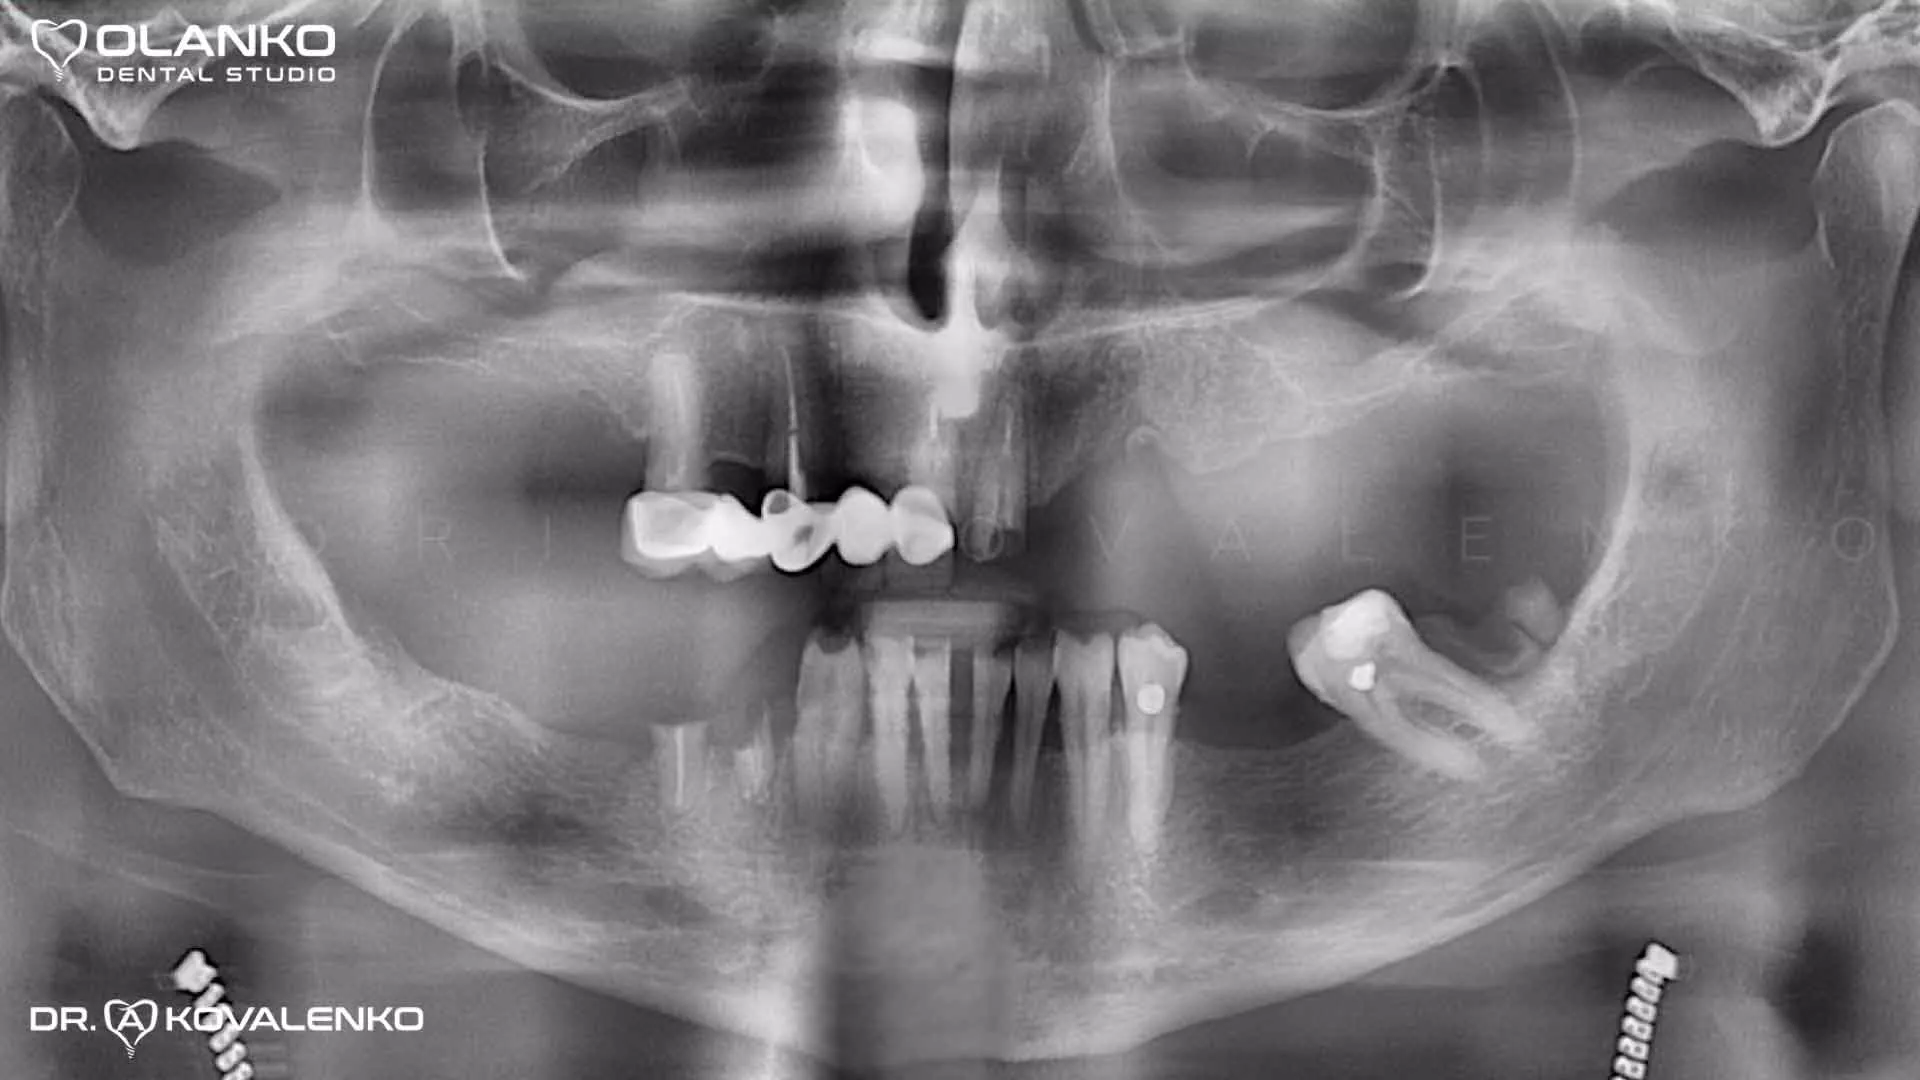

Пациент обратился с жалобой на невозможность жевания и проблему с эстетикой улыбки,в связи с потерей и разрушением 80% зубов в полости рта

Фото ситуация  ДО начала лечения